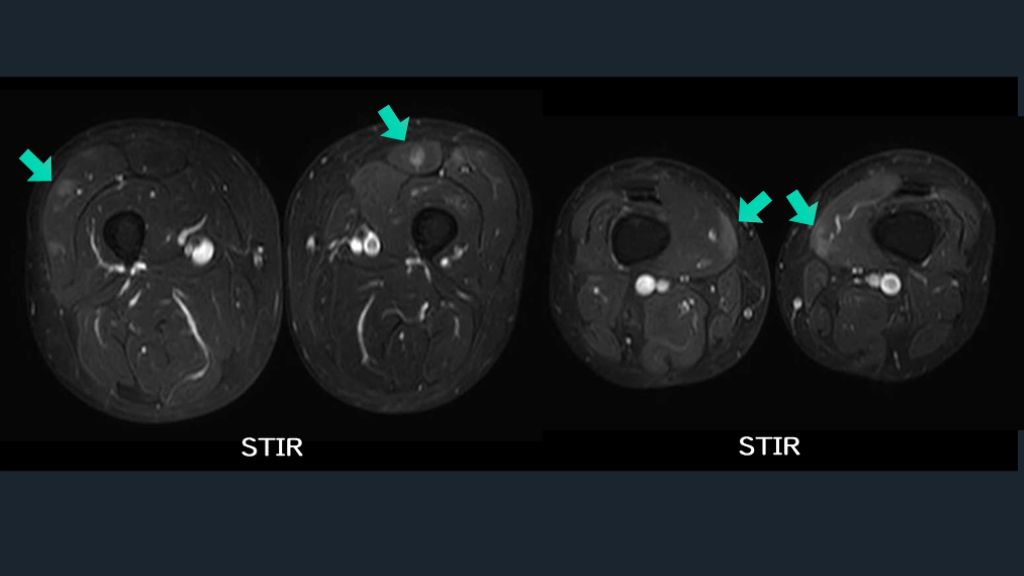

純粋運動障害を来す筋炎。 筋炎の傍証として、 大腿筋MRIをとってみる。 TIPS

CASE 比較的突発発症の両下肢麻痺の40歳男性例。 脊髄障害を考慮して脊髄MRI施行するが所見なし。 大腿部痛も訴える。両下肢MMT 2/5。 GBS?脊髄障害?どうする?運動感覚障害とはいい難し。 やや節操ないが、大腿筋MRIを施行し、筋障害を証明した。

Ann Rheum Dis. 2016;76:681–687. 筋MRI 客観的に筋炎所見があること どの筋に障害があるか? 脂肪変性はあるか? 急性か?慢性か? など、客観的に知ることができる。

STIR STIR

客観的な検査に頼る。筋障害を筋MRIでみる。 ERでどこまでやるか?はもちろん議論にはなる。 筋障害は外からみてもわかりにくいこともある。 筋萎縮あるかも???といってもわかりにくい。 筋MRIが教えてくれること:急性筋障害があることの証明。また慢性的な筋障害の証拠(脂肪置換や変性)。 筋力障害が分からないときの筋MRIは一考。 CTでも筋萎縮に注目するのもオススメ。 解説